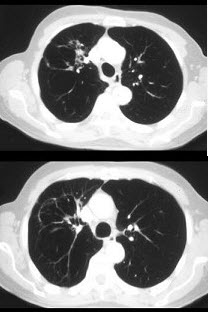

[单选题]该病例为少见病,正确的诊断为()A .局灶性肺气肿B .肺隔离症C .肺炎D .肺胚胎发育变异E .以上都不是

[单选题]该病例为少见病,正确的诊断为()A.局灶性肺气肿B.肺隔离症C.肺炎D.肺胚胎发育变异E.以上都不是